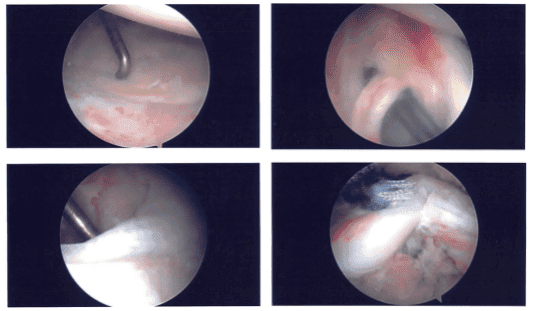

Intraoperative images

Examination of the glenohumeral joint showed a large rotator cuff tear. It also showed partial tearing and inflammation of the biceps’ tendon. Decision was made to not do the biceps and do a mini-open biceps tenodesis later.

Examination of the cartilage showed grade 1 osteoarthritic changes of the glenoid surface. There was fraying of the labrum, which was debrided with the use of a shaver. There was fraying of the subscapularis tendon, which was also debrided with the use of the shaver.

The arthroscope was inserted into the subacromial space. Subacromial bursectomy was performed with the shaver. This was followed by acromioplasty with the use of Coblation wand followed by a 6.0 burr incising the acromial spur, osteoarthritis of the AC joint was also present, which was again cleaned with the use of a Coblation wand followed by 6.0 burr excising about a centimeter of the distal clavicular through the posterior as well as anterior superior portal.

A lateral entry portal was made for the repair of the rotator cuff. The debridement of the rotator cuff was done. Also, the superior surface of the head of humerus was cleaned and debrided with the use of burr for the preparation for the repair of the rotator cuff.

Good apposition and repair of the rotator cuff was achieved. The sutures were cut. Final pictures were taken and saved. The shoulder was thoroughly irrigated and drained. Arthroscope was removed and the patient’s arm was taken out of traction. A subpectoral approach was planned for the biceps tenodesis.

After discussing treatment options, we have decided to proceed with formal physical therapy as well as a home exercise program for rehabilitation of the shoulder. We went over the arthroscopic pictures and removed the stitches during the visit.